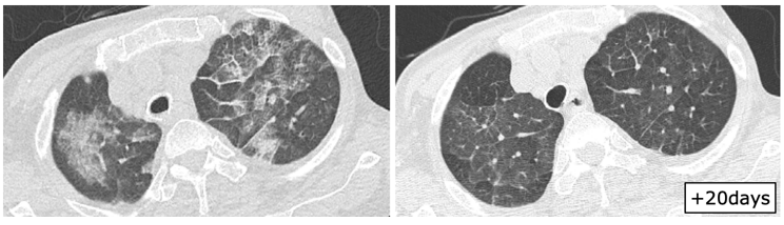

日本一项研究总结了血液系统疾病和造血干细胞移植患者RSV感染的影像学表现,其中一例63岁T淋巴细胞瘤患者感染RSV后症状持续10天,右肺下叶支气管处支气管管壁增厚,经过治疗,情况有所改善(图1)。图2为一例75岁T细胞淋巴瘤患者,起病9天,肺上叶可见小叶中心结节影(图2)。23岁急性粒细胞白血病患者早期影像学表现为多叶段沿支气管束分布的磨玻璃影,随着时间的延长以及治疗的开展,病变密度逐渐增加、皱缩及吸收(图3)。图4为一例78岁慢粒患者,羟基脲治疗,起病1天,影像学可见铺路石征,随着时间的延长,逐渐吸收(图4)

图片

图2  75岁T淋巴细胞瘤患者感染RSV的影像学表现

图源:Intern Med. 2020;59(2):247-252.